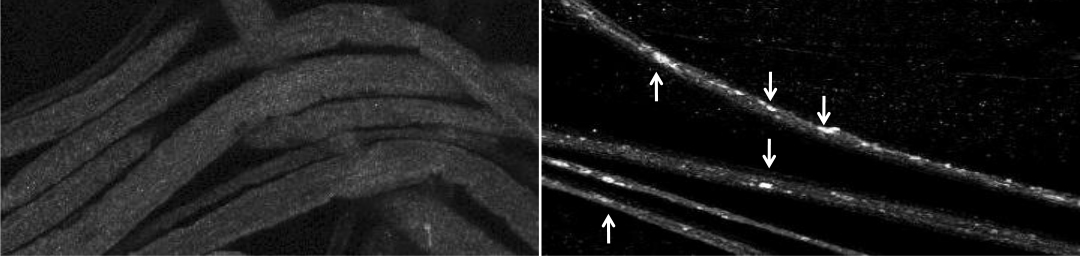

Materials move smoothly through the brain cells of a fruit fly larvae (left). But when scientists reduced the levels of the protein presenilin and the enzyme GSK-3B present in the nerve, tiny organic bubbles called vesicles began moving in an uncoordinated fashion and became trapped (right). Credit: Shermali Gunawardena.

When researchers lowered the amount of presenilin in the neurons of fruit fly larvae, less GSK-3ß became activated and vesicles began speeding along cells in an uncontrolled manner.

Decreasing levels of both presenilin and GSK-3ß at once made things worse, resulting in “traffic jams” as the bubbles got stuck in neurons.